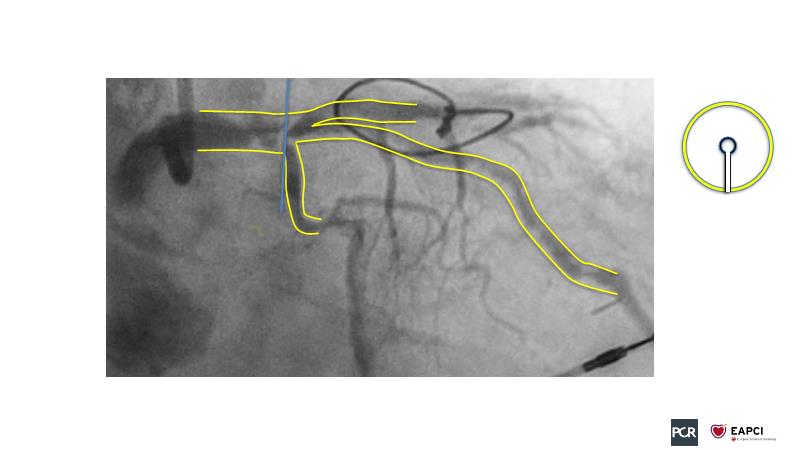

The aim of this session is to address the question of how to optimise outcomes for high-risk patients by analyzing two real-life cases for discussion: a distal calcified left main trifurcation and a high-risk PCI with orbital atherectomy.